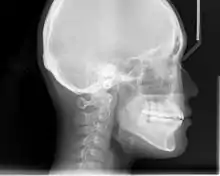

An X-ray taken for skull analysis